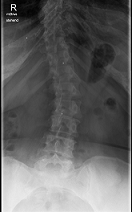

Röntgenbilder

- LSPINE

- unbenannt nochmal verkleinert.png (25.52 KiB) 19749 mal betrachtet

deine Bilder lassen vermuten, dass vielleicht gar nicht die Skoliose dein Problem ist, sondern dein sagittales Profil. (Steht dein Kopf ziemlich nach vorne, wenn du dich vin der Seite betrachtest?) solltest auf jeden Fall einmal zum Spezialisten, im deine Situation kompetent abklären zu lassen. Aus NRW ist wahrscheinlich Dr. Verres in Bingen am nächsten.

mit dem sagittalen Profil meint man das Profil von der Seite gesehen. Laut deinen Aufnahmen hast du eher eine geringe Skoliose, aber einen ziemlichen Rundrücken und Hohlkreuz was auch Beschwerden machen kann und das die Ärzte auch gerne übersehen oder nicht sehen wollen. Deshalb ist es auch wichtig, einen Spezialisten aufzusuchen, der dies auch mit behandeln kann. Leider ist dies keine Ganzaufnahme, dann würde man das eher sehen. Es gibt hier schon genug Berichte, die das mit Hyperkyphose und -lordose gut beschreiben. Also lesen bildet...

Dem kann ich mich nur anschliessen, es sieht sehr nach Rundrücken (Bild 2-Hyperkyphose) und Hohlkreuz (Bild 1-Hyperlordose) aus.sloopy hat geschrieben:deine Bilder lassen vermuten, dass vielleicht gar nicht die Skoliose dein Problem ist, sondern dein sagittales Profil.